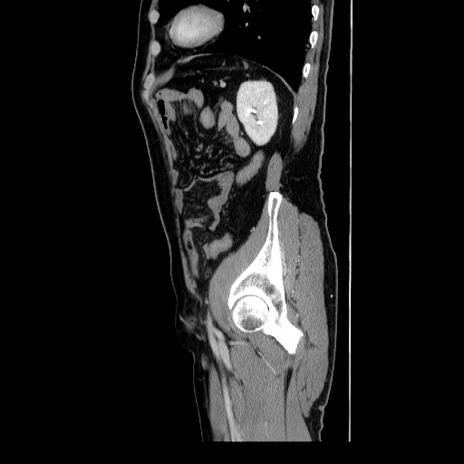

症例34(矢状断像)

冠状断像